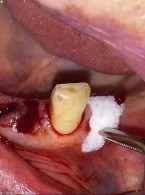

Podczas leczenia endodontycznego zęba 37 (dolny lewy drugi ząb trzonowy żuchwy) u 48-letniego mężczyzny pacjent zasygnalizował ból. Doszło do tego w trakcie wypełniania kanału korzeniowego pastą jodoformową. Ból obejmował lewą stronę twarzy, promieniował do pozostałych zębów lewej strony żuchwy i do okolicy lewego kąta ust. Na zdjęciu zębowym wykonanym bezpośrednio po pojawieniu się bólu zdiagnozowano zacienienie rzutujące się w przebiegu kanału żuchwy. Jakie powinno być postępowanie po przepchnięciu materiału do kanału żuchwy i jak można uniknąć takiego powikłania?